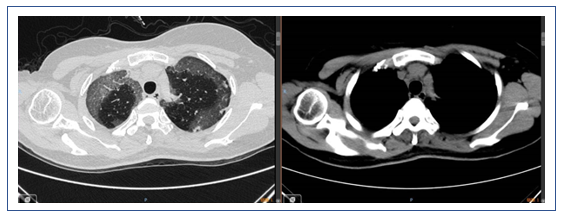

经过治疗后,该患者的氧合有所改善,胸部CT提示肺部磨玻璃影明显吸收,但斑片状实变影愈加明显。此外,还出现了少量的胸腔积液。所以还是考虑患者有无潜在的血管炎或结缔组织疾病。由于患者的血管病变比较突出,D-二聚体和肿瘤标志物水平升高。所以暂时不能除外淋巴瘤或血管相关肿瘤。此时可以考虑行支气管肺泡灌洗,同时取标本送病理检查。

该患者经过短期治疗后,肺部磨玻璃影明显吸收。这种效果应是来源于糖皮质激素的作用。除了血管炎是否也要考虑皮肌炎的可能,可以做皮肌炎抗体检查。另外,建议患者行支气管肺泡灌洗和NGS检查。患者胸部CT显示双下肺背段有斑片影,这或许与患者机械通气时间长有关,可能为重力依赖区斑片渗出影。